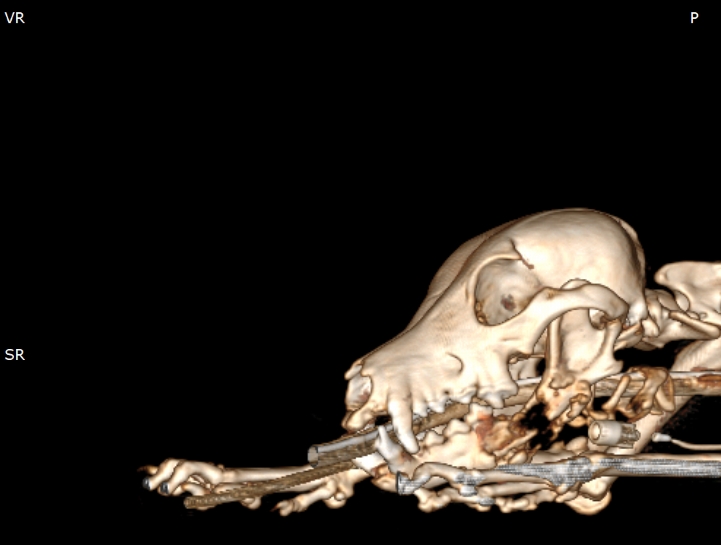

狗狗電腦斷層掃描 不明原因口腔出血 嚴重牙周病 口腔惡性腫瘤 鱗狀上皮細胞癌(Squamous cell carcinoma,SCC)

主訴嘴巴突然流血 口腔潰爛 左下顎腫脹 同時有嚴重牙周病 經由口腔採樣 電腦斷層掃描 確認為鱗狀上皮細胞癌(Squamous cell carcinoma,SCC)同時已經侵犯下顎骨。確診後經由外科醫師、腫瘤科醫師、電腦斷層影像科醫師共同擬定治療計畫後

,大範圍切除左下顎,經過一年追蹤,目前狗狗一切安好喔。

*電腦斷層影像

頭骨結構較為複雜 頭骨骨折相對於四肢長骨骨折 不容易靠xray 完整評估術前需要靠電腦斷層影像檢查評估骨折狀況才能良好評估手術方式 提高成功率